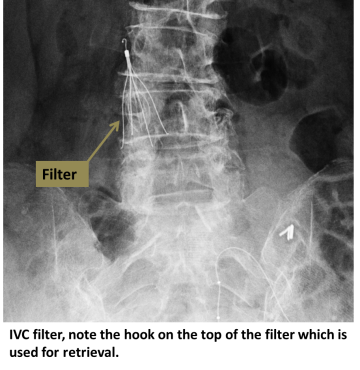

An interventional radiologist uses ultrasound to access the jugular vein at the neck, or the femoral vein at the groin. Contrast dye is injected to determine size and anatomy of the IVC. The filter is then deployed at the appropriate position in the IVC, where small hooks affix it to the wall.

Most IVC filters are retrievable. Once the filter is no longer needed, contact your interventional radiologist to arrange removal of the filter.